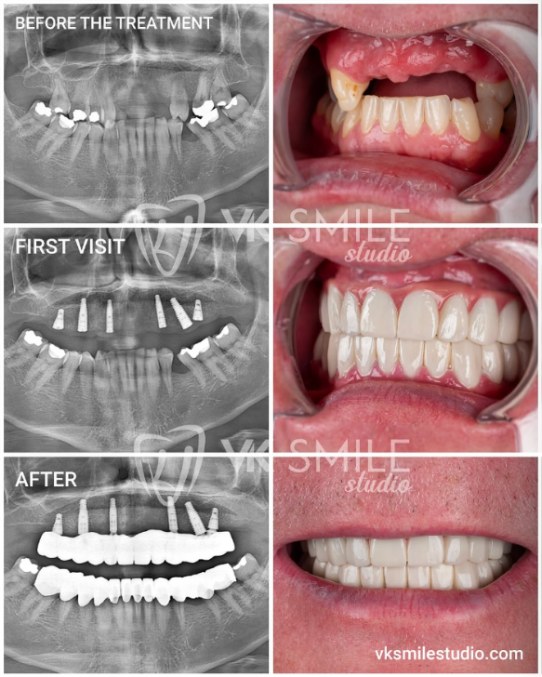

- Verified patient reviews with dated before-and-after photos.

- Clear implant brand disclosure (Straumann, Nobel, Zimmer, Megagen, etc.).